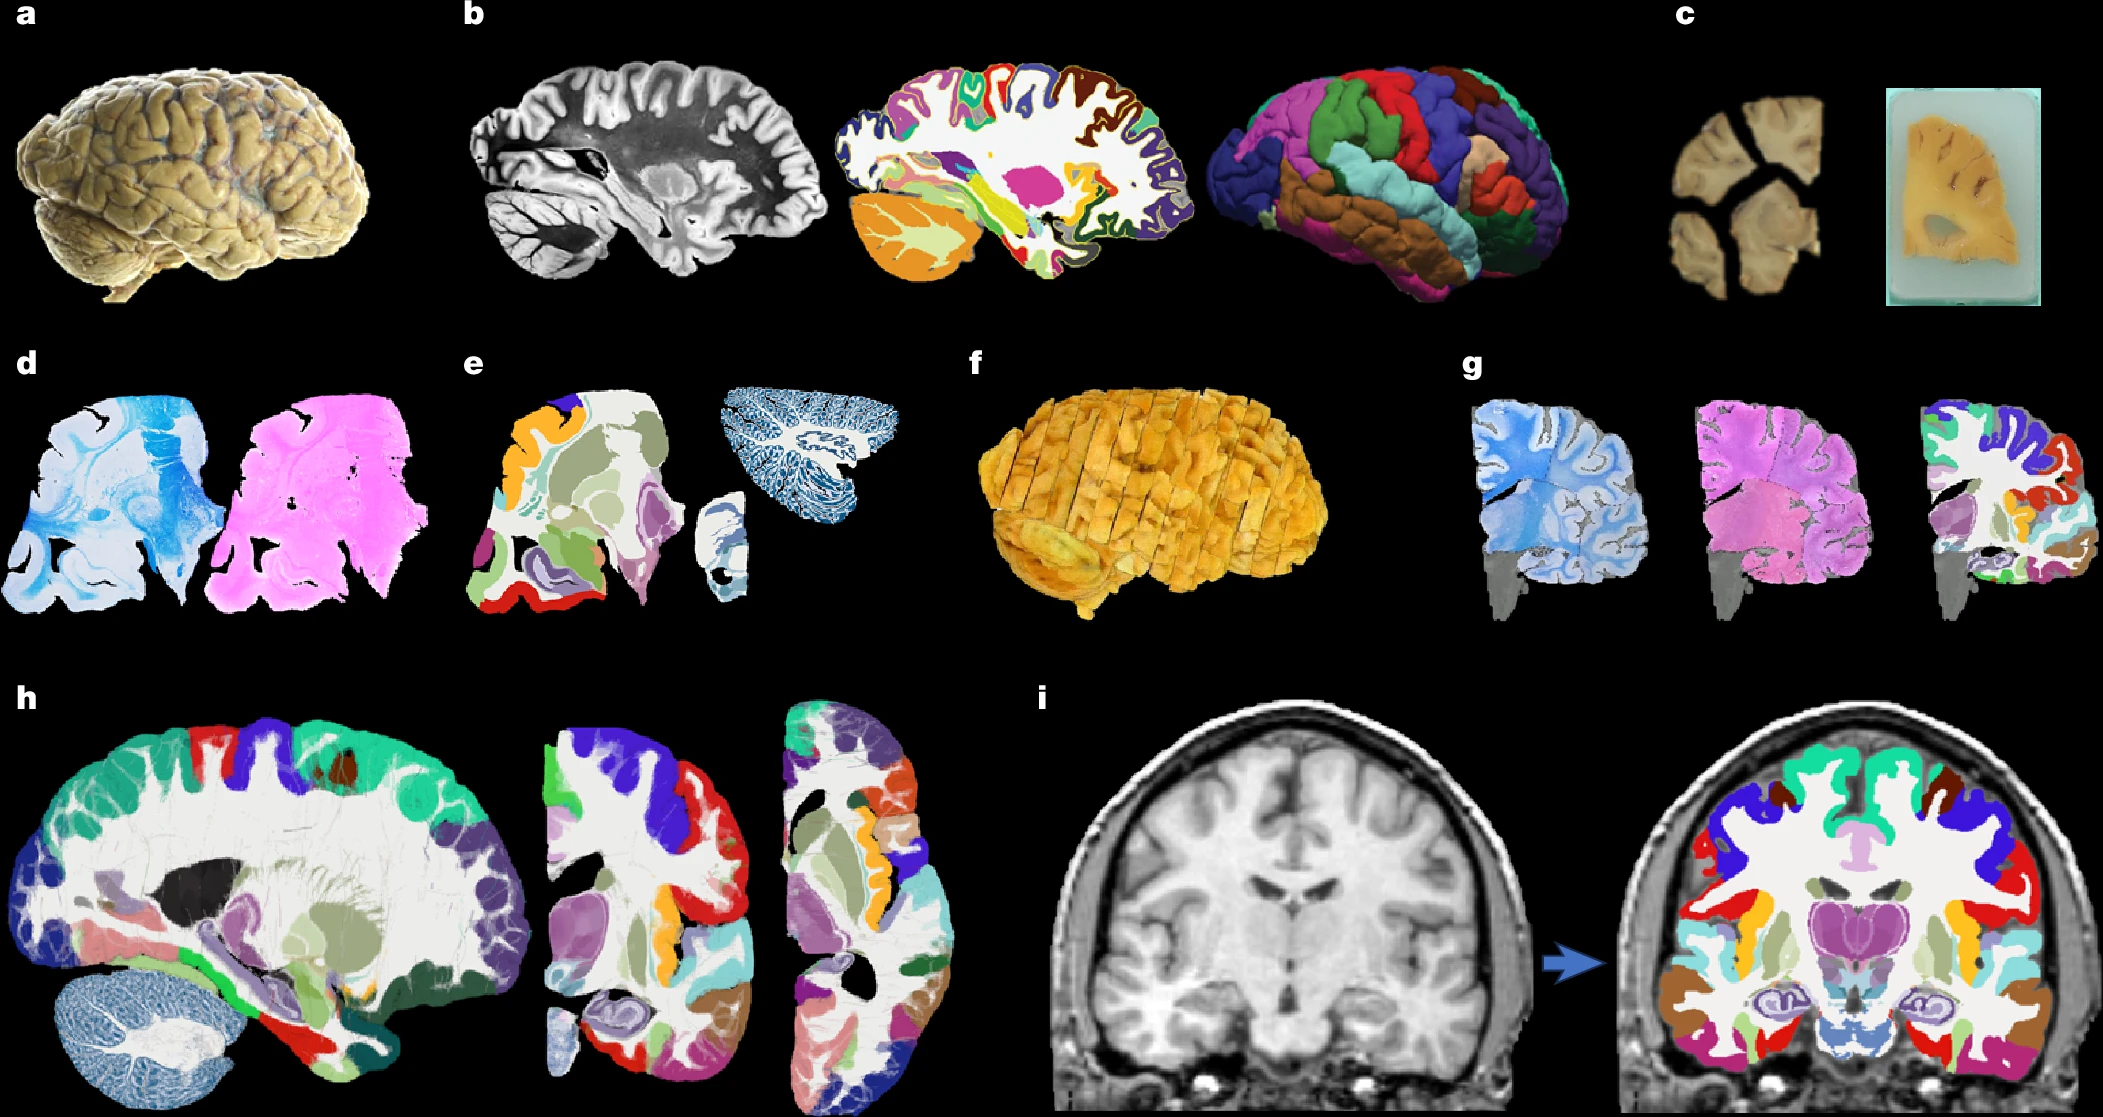

Атлас NextBrain создан на основе анализа изображений, полученных с помощью высокоразрешающей ex-vivo МРТ, которая проводилась на реальных гистологических образцах мозга. Это позволило получить высокодетализированные данные о структуре мозга.

Исследователи взяли полушария мозга пяти посмертных доноров, подготовили тысячи гистологических срезов, которые окрасили специальными красителями, отражающими разный клеточный состав мозговых структур. С помощью искусственного интеллекта они собрали эти тысячи плоских «картинок» обратно в единую трехмерную модель, убрав все искажения, возникшие при нарезке. Вручную и с помощью искусственного интеллекта авторы разметили на этой модели 333 различные области интереса (кору, подкорковые ядра, отделы гиппокампа, миндалины и т.д.).

В результате удалось получить инструмент NextBrain, который позволяет анализировать разные участки мозга, причем делает это с определенной вероятностью, что отражает реальную, «размытую» природу границ в биологических тканях, и чего ранее существовавшие инструменты не позволяли делать. Ранее известный атлас MNI позволял выделять только 138 областей интереса.

Кроме того, ученые создали и выложили в открытый доступ не только сам атлас, но и все исходные данные, а также инструмент для автоматической сегментации. Теперь любой исследователь, загрузив стандартный МРТ-снимок, может всего за полчаса получить его детализированную разметку на все 333 области интереса.